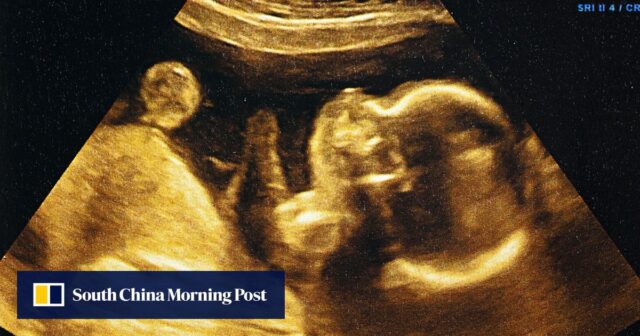

Uma equipe liderada pela China construiu o primeiro miniútero do mundo em um chip que pode imitar totalmente a “invasão” de embriões humanos no útero durante o início da gravidez.

Os blastocistos são embriões de cinco a seis dias de idade que consistem em 100 a 200 células que se dividem rapidamente, incluindo uma massa celular externa que se implantará na placenta para se desenvolver em uma placenta e uma massa celular interna que eventualmente formará o feto.